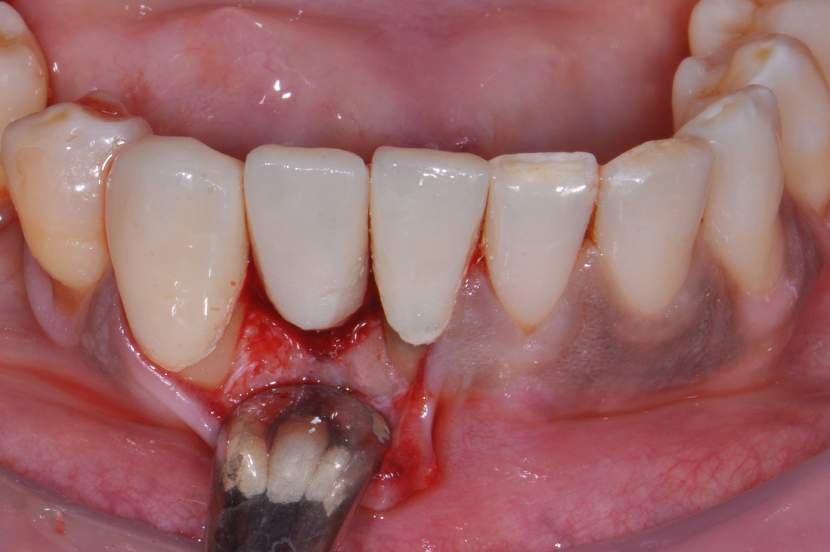

Os implantes Slim Pilar, apresentam alta versatilidade protética possibilitando aplicação de coroas Cimentadas ou Parafusadas (Fig. 3). O Sistema protético é simplificado, utilizando o mesmo sistema aplicado em implantes Implacil Cone Morse para transferentes, coifas e análogos. E a aplicação é tanto para elementos Unitários como para Múltiplos.

O implante de corpo único de diâmetro pequeno tem várias vantagens quando utilizado para substituir incisivos laterais superiores e incisivos inferiores. O design de uma peça, elimina o risco de afrouxamento do parafuso do pilar. Uma vez que não há micrograp entre o pilar e implante, e a quantidade de perda de óssea crestal pode também ser reduzida.6